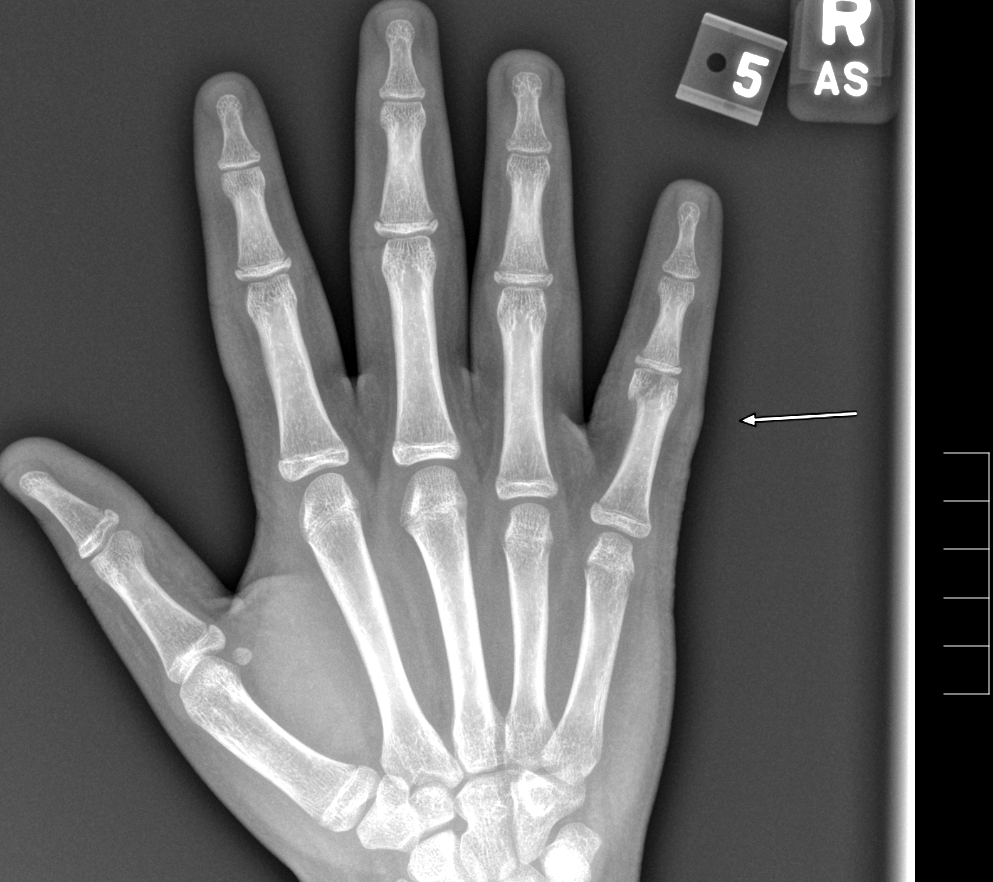

Info Images Findings Impression Reco/Acuity Case Images View Images / Launch Visage Case Notes History 2-month-old presents with decreased right arm movement, increased fussiness, and increased sleepiness for 2 days. Suspected non-accidental trauma. Exam Skeletal survey Prior Study none Dicom View Reference Material

Section 1 Submit Findings CB1550 Findings Skeletal Survey - Technique Check Skull AP/Lat Yes No Cervical and Thoracolumbar spine Yes No Chest X-Ray Yes No Ribs – Left/Right Oblique Yes No Abdominal X-Ray Yes No Pelvis with both hips Yes No Bilateral Humerus, Forearm, Hand Yes No Bilateral Femur, Tibia/fibula, feet Yes No Any additional lateral views of the extremities Yes No The exam is over or under penetrated. Yes No The exam may or may not be limited by overlying structures or soft tissues, body habitus, patient positioning, support devices, or motion. Yes No The area of concern is indicated by the patient, technologist, or care provider. Yes No The area of concern is included on the exam. Yes No Soft Tissues There is soft tissue swelling, indistinctness of fat/muscle planes, gas, or laceration in the area of clinical concern. Yes No There is an effusion, fat pad displacement, or fat fluid level. Yes No There is a radiodense or lucent foreign body. Yes No There are other densities, calcifications, post-surgical changes, or support devices in the soft tissues. Yes No Any support lines/tubes. Yes No Bone There is a break or interruption of the continuity of the cortical or cancellous bone. Yes No There is overriding of the trabeculae with apparent sclerosis. Yes No There is displacement of a fracture fragment. Yes No There is bowing of the bone in addition to the fracture at the apex of the bowed bone concerning for the greenstick. Yes No There is a spiral fracture of the leg concerning for toddler’s fracture. Yes No There is abnormal angulation or bulging of the cortical surface relative to the normal cortex which could be from a buckle or torus fracture. Yes No There is a displaced fragment which may be from avulsion by a tendon, ligament, or joint capsule or from a comminuted or other fracture. Yes No The stress trabeculae or other trabeculae of the cancellous bone are interrupted or otherwise abnormal. Yes No There is subperiosteal or endosteal reaction which could indicate a healing or subacute fracture or other abnormality. Yes No There is hard/soft callus formation. Yes No There is remodeling of the bone. Yes No There is a corner fracture or metaphyseal lesion that could be from nonaccidental trauma. Yes No There are multiple fractures of different ages. Yes No There are vertebral body/spinous process fractures. Yes No There are rib fractures. Location - posterior or lateral. Yes No There is scapular/sternal fracture. Yes No There are fractures of the digits. Yes No There are wormian bones. Yes No There are intrasutural bones. Yes No There is metaphyseal abnormality (lucencies, increased density, erosion) which may be from something other than injury such as stress, metabolic disease (e.g. rickets with loss or distortion of the zone of the provisional calcification), neoplasm (e.g. leukemia), heavy metals, inflammation, or infection. Yes No There are metaphyseal spurs. Yes No There are bony deformities involving multiple bones. Yes No The bones are gracile. Yes No There are non-healing fractures. Yes No There is/are focal or multifocal lytic/lucent, blastic/sclerotic or mixed density lesion(s) or other abnormality. Yes No Overall bone density is increased or decreased with or without thinning or thickening of the cortical or cancellous bone. Yes No Growth plates, ossification centers, apophyses The growth plate(s) is/are abnormal. Yes No There is widening of the physis from a fracture with or without displacement of the epiphysis (Salter-Harris I). Yes No There is a fracture through the physis which then extends into the metaphysis with or without angulation or displacement (S-H II). Yes No There is a fracture through the physis which then extends into the epiphysis and is intra-articular, with or without angulation or displacement (S-H III). Yes No There is a fracture through the metaphysis, physis, and epiphysis which extends into the joint space with or without angulation or displacement (S-H IV). Yes No There is narrowing of the physis from a compression fracture (S-H V). Yes No The apophysis, epicondyle, secondary ossification center, or accessory ossicle is displaced or otherwise abnormal. Yes No The ossification centers are underdeveloped. Yes No Joints and alignment There is an effusion, fat pad displacement, or fat fluid level. Yes No The epiphysis or subchondral bone is fractured, interrupted, flattened, compressed, impacted, displaced, or otherwise abnormal. Yes No There is an intra-articular loose body or chondrocalcinosis. Yes No The joint is widened, narrowed, dislocated, malaligned, or incongruent. Yes No There is pseudoarthrosis. Yes No Other findings There are developmental changes or other anatomic variants or other existing conditions that may or may not be contributing to symptoms which can or should be further evaluated non-emergently or are otherwise incidental. Yes No The remainder of the exam is abnormal for age. Yes No The lungs show focal airspace opacity. Yes No There is pneumothorax. Yes No There is organomegaly. Yes No There is intra-abdominal calcification. Yes No There is displacement of the bowel loops. Yes No There is free intraperitoneal air. Yes No The bowel loops are dilated/obstructed. Yes No There is paraspinal soft tissue abnormality. Yes No